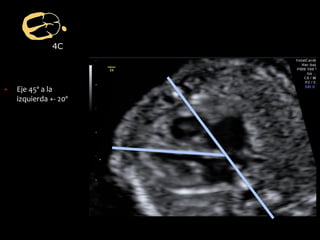

dad

▪ Eje 45º a la

izquierda +- 20º